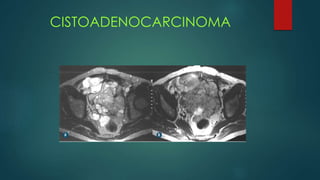

CISTOADENOCARCINOMA